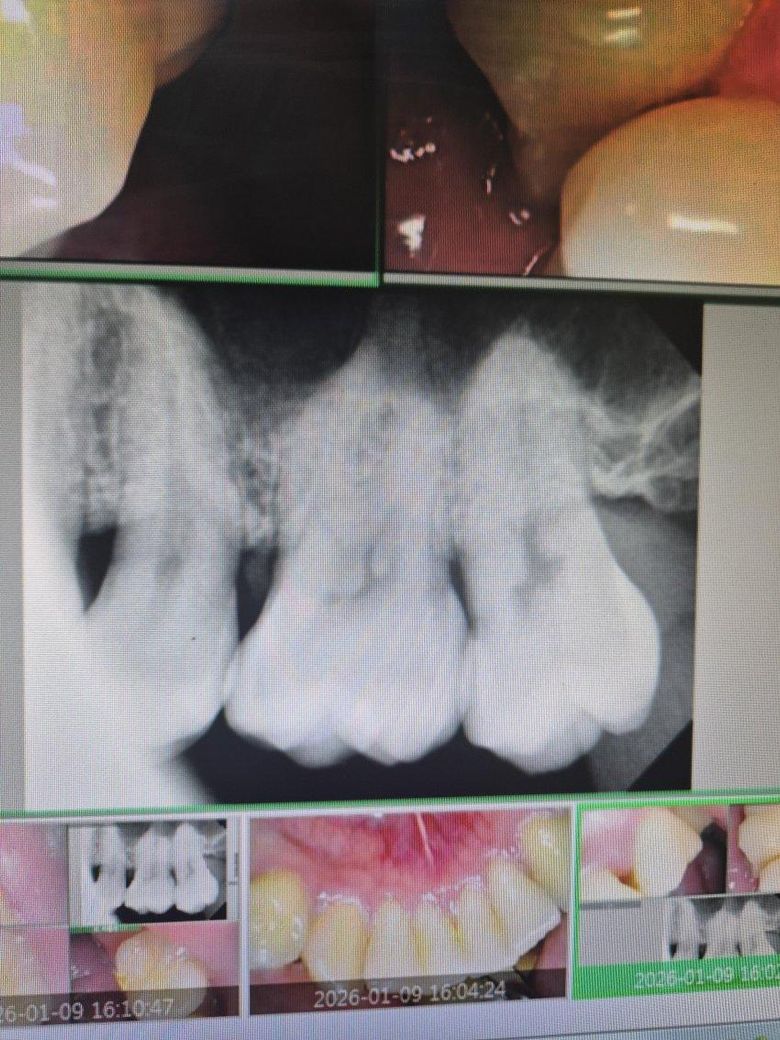

혹시 인접면충치가심한가요 답변부탁드립니다 ㅜㅜ

윗쪽 맨왼쪽어금니입니다 현재 이가시린상태인데 제가갓던병원에서는 인접면초기충치는맞는데 아직 치료할단계는아니라고 하셔서 시린이약과 불소만 바르고 나왓습니다 다른분들은 어떻게 생각하시나요??

사진으로만 봤을 경우에는 인접면의 충치가 커보이지는 않습니다.

충치가 초기이고 한다면 치료를 하지 않은 상태에서 관리를 할수도 있습니다.

1. 네 아직 치료할 정도의 충치로 보이진 않습니다